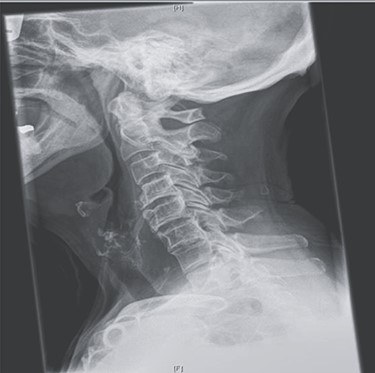

The patient underwent an anterior cervical osteophytectomy through an anterolateral approach (Fig. 2). Because of the advanced age and stable cervical vertebrae, no fusion or osteosynthesis was performed. No post-operative complications were encountered. Post-operative controlled X-ray examination revealed adequate resection of osteophytes (Fig. 3). Oral intake gradually advanced as tolerated. The patient was discharged on the third post-operative day without any neurological deficits. No evidence of recurrence was detected on lateral cervical X-ray examination, and the patient was free of symptoms at the 1-year follow-up.